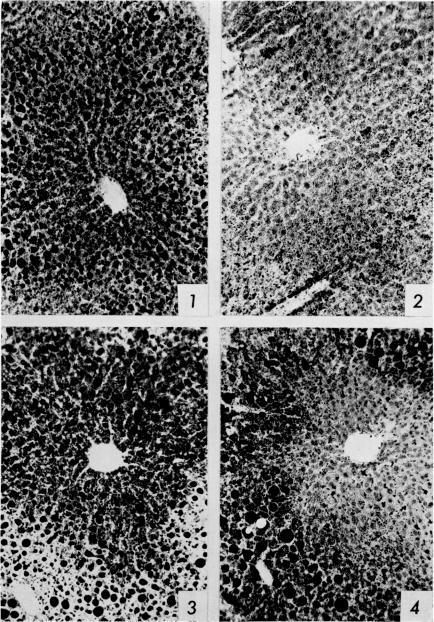

The nature of dietary fat and the pattern of hepatic liposis in choline-deficient mice.

https://cdn.ncbi.nlm.nih.gov/pmc/blobs/7973/2603997/b23581656c56/yjbm00632-0008-a.jpg